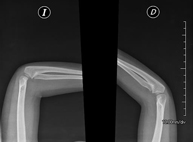

- RX Extremitats

Tècnica que usa els raigs X a través de la qual s'obtenen imatges de l'interior de les extremitats per al seu estudi, especialment dels ossos. Indicacions: traumatisme, infeccions articulars. - RX Artrografia

Tècnica que usa els raigs X a través de la qual s'obtenen imatges de la totalitat d'ambdues extremitats inferiors per al seu estudi, amb la valoració especialment de la presència de dismetries entre elles. - RX Extremitats

Tècnica que usa els raigs X a través de la qual s'obtenen imatges d'ambdues extremitats per al seu estudi. - RX Malucs